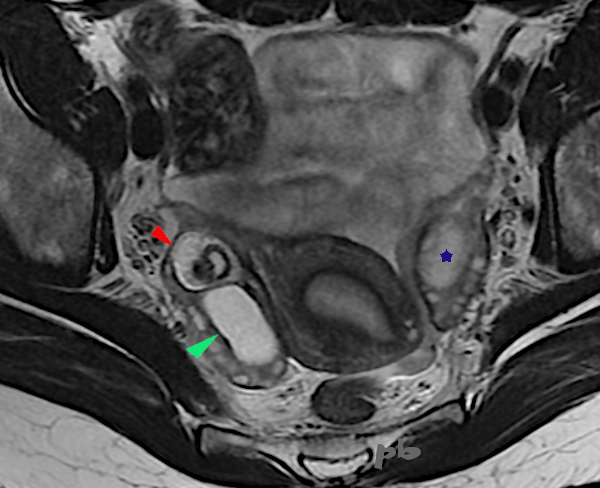

18 – Diagnostic différentiel IRM – Saignement intra-folliculaire

(Même patiente que 17)

IRM coupe axiale T1.

Hypersignaux T1 intra-folliculaires (►) : sang.

19+20+21- Kystes endométriosique et dermoïde – IRM

Sémiologie IRM comparative entre un kyste endométriosique (►) et un kyste dermoïde (►), tous les 2 ovariens droits. Ovaire gauche porteur d’un follicule dominant (★).

| T2 (image 19) | T1 sans fatsat (image 20) | T1 avec fatsat (image 21) | |

| Endométriome (►) | hypersignal | hypersignal | hypersignal |

| kyste dermoïde (►) | Hypersignal Nodule central hyposignal | Hypersignal Nodule central hyposignal | Hyposignal Nodule central hyposignal |

Le kyste dermoïde contenant de la graisse, il apparait en noir, sur la séquence T1 fatsat (qui supprime le signal de la graisse). Alors que le signal du sang ne se modifie pas. Les autres tissus contenant de la graisse ((sous-cutanés par exemple) deviennent également noirs.

L’hypersignal en T2 du kyste endométriosique n’est pas très fréquent, ni caractéristique, au contraire du »shading ». L’hypersignal en T1 fatsat permet le diagnostic.